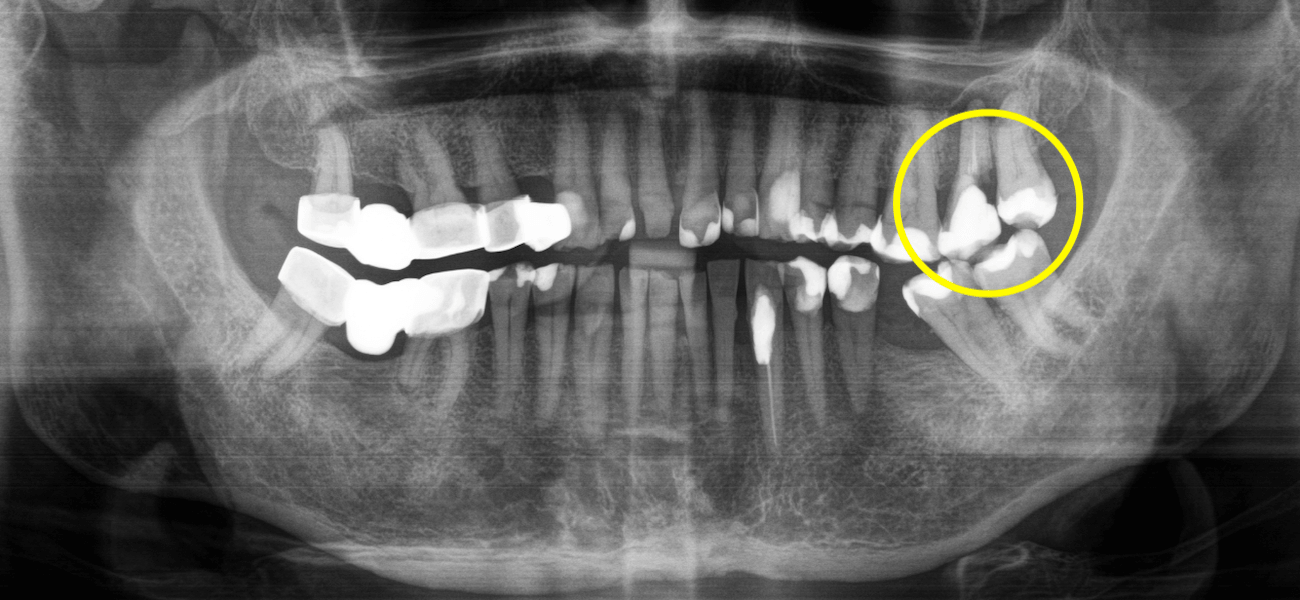

Нависающий край — это ситуация, когда пломба или коронка выступает за пределы естественного контура зуба. Чаще всего это происходит в межзубной области, иногда ниже уровня десны. Обычно это трудно почувствовать языком и не видно в зеркале. Один из возможных сигналов, который иногда появляется, — флосс начинает застревать, рваться или проходит иначе, чем раньше.

Проблема в том, что такой край создаёт участок, где налёт задерживается, а убрать его значительно сложнее. Это актуально и для пломб, и для коронок: если край заходит под десну или выходит за контур зуба, он начинает влиять на ткани. В результате в этой зоне накапливается биоплёнка, которую трудно удалить, и это поддерживает воспаление десны.

Если это продолжается долго, воспаление не ограничивается только десной. Оно может распространяться глубже: постепенно десна начинает отходить от зуба, уменьшается костная поддержка. Поэтому нависающие межзубные реставрации — независимо от того, пломба это или коронка, — стабильно связаны с худшими пародонтальными показателями: большей кровоточивостью, более частым гингивитом и более выраженной потерей кости.